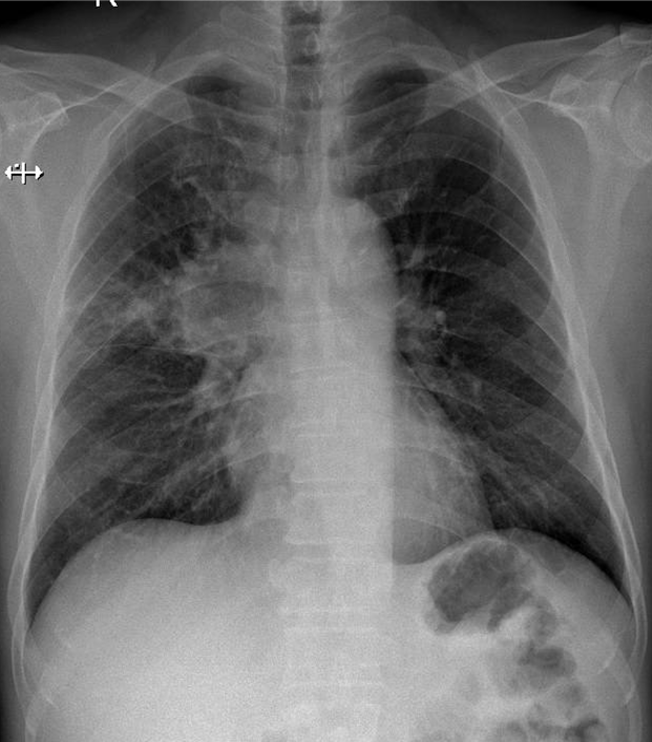

Hãy phân tích tình huống Nam 66 tuổi

1-Thâm nhiểm phế nang thùy trên phổi (P) => Viêm phổi 2-U rốn phổi (P)